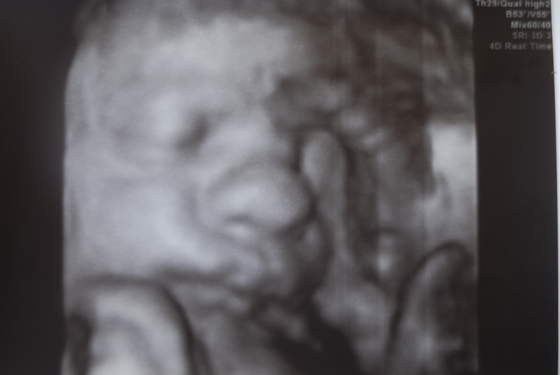

Jaspis 3d to masz tylko zdjęcia a w 4d też ruchy dziecka-taki mini filmik ;-)ja mam 3/4d za tydzień to bedzie prawie 24 tydzień wiec myślę że coś się zobaczy jak oczywiscie maluch bedzie chciał współpracować. dzięki dziewczyny za wsparcie-myslałam że tylko ja mam podwyższone białwe krwinki a z tego co widze to wiekszość wiec juz sie nie martwie